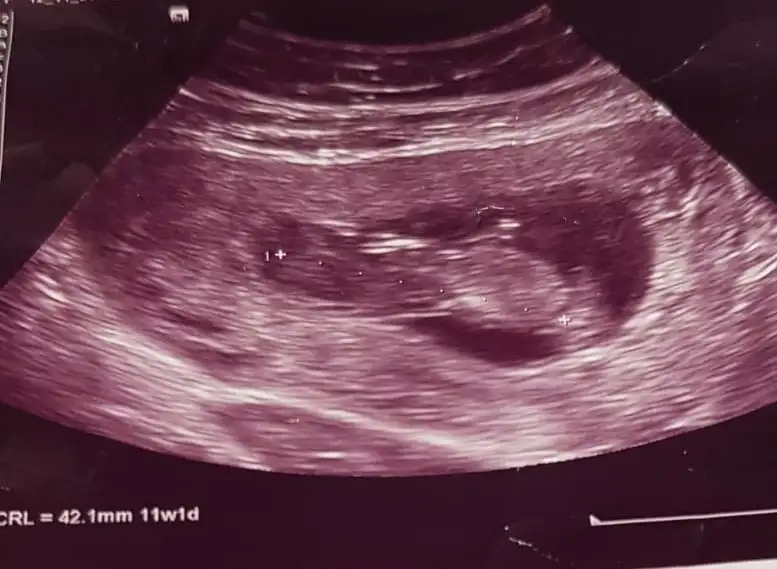

Sizce bana kız gibi geldi arkadaşlar tahminleri alalım:anneadayı:

Eklentiler

• 0ECABA96-7800-45A3-B34E-E6A90A9D5C9A.webp

0ECABA96-7800-45A3-B34E-E6A90A9D5C9A.webp

27,9 KB · Görüntüleme: 102